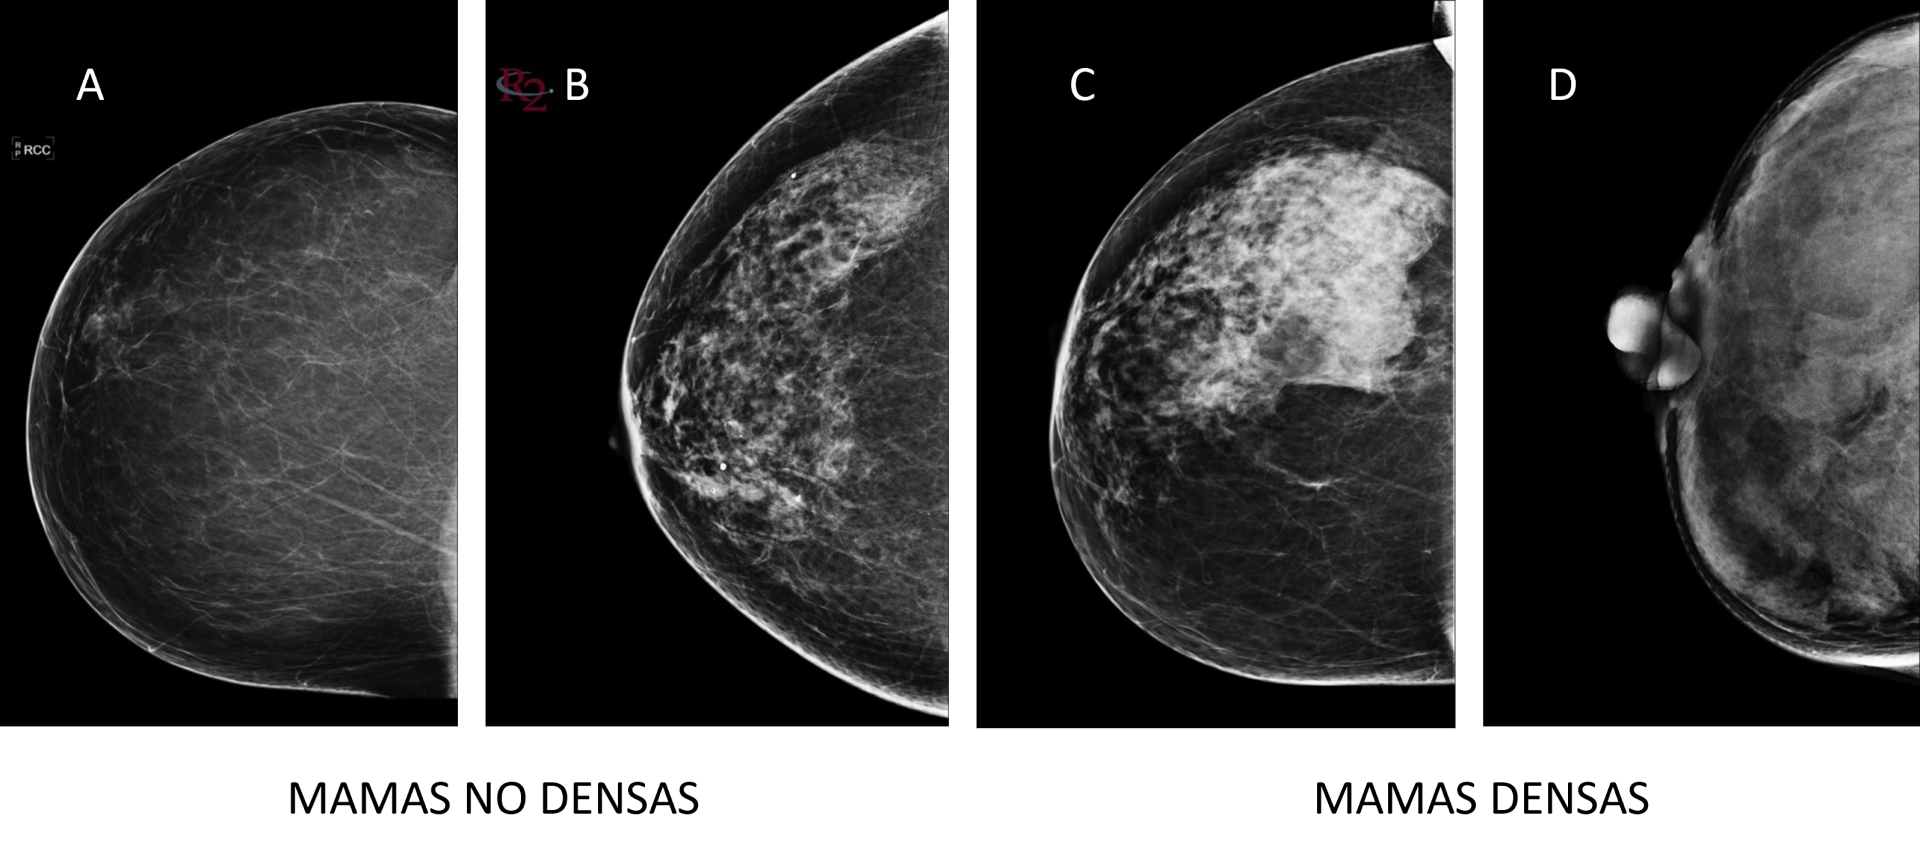

La densidad mamaria simplemente describe de qué está hecha tu mama: cuánto tejido “firme” (glandular y fibroso) tienes en comparación con grasa. En las mamografías, la grasa se ve oscura, y el tejido más firme aparece blanco… igual que los tumores. Por eso, cuando una mamografía se ve muy blanca, decimos que son mamas densas. No significa que haya ninguna enfermedad: es solo una característica natural de cada mujer.

Los radiólogos dividen la densidad en cuatro categorías (A, B, C y D) siguiendo el sistema BI-RADS:

• A: casi toda grasa

• B: algo de tejido denso

• C: bastante tejido denso

• D: extremadamente denso

Se considera que tienes mamas densas si estás en C o D. Esto es frecuente en mujeres jóvenes o delgadas, y suele bajar con la edad.

Fuente imagen: libro “Imagen Médica en Patología Mamaria”, una colaboración entre la Universidad Complutense y la Fundación Tejerina